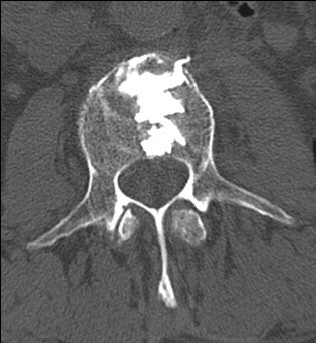

![]() |

Eighty-year-old man with renal cell carcinoma who presented with lower back pain. Control CT scan (below) acquired immediately after vetebroplasty shows homogenous cement distribution in tumor necrosis with small ventral leakage. Control radiography (above) acquired three months after procedure shows stable vertebral body with unchanged location of cement filling. Schaefer O, Lohrmann C, Markmiller M, Uhrmeister P, Langer M, "Combined Treatment of a Spinal Metastasis with Radiofrequency Ablation and Vertebroplasty," (AJR 2003, Vol.180, pp.1075-1077).